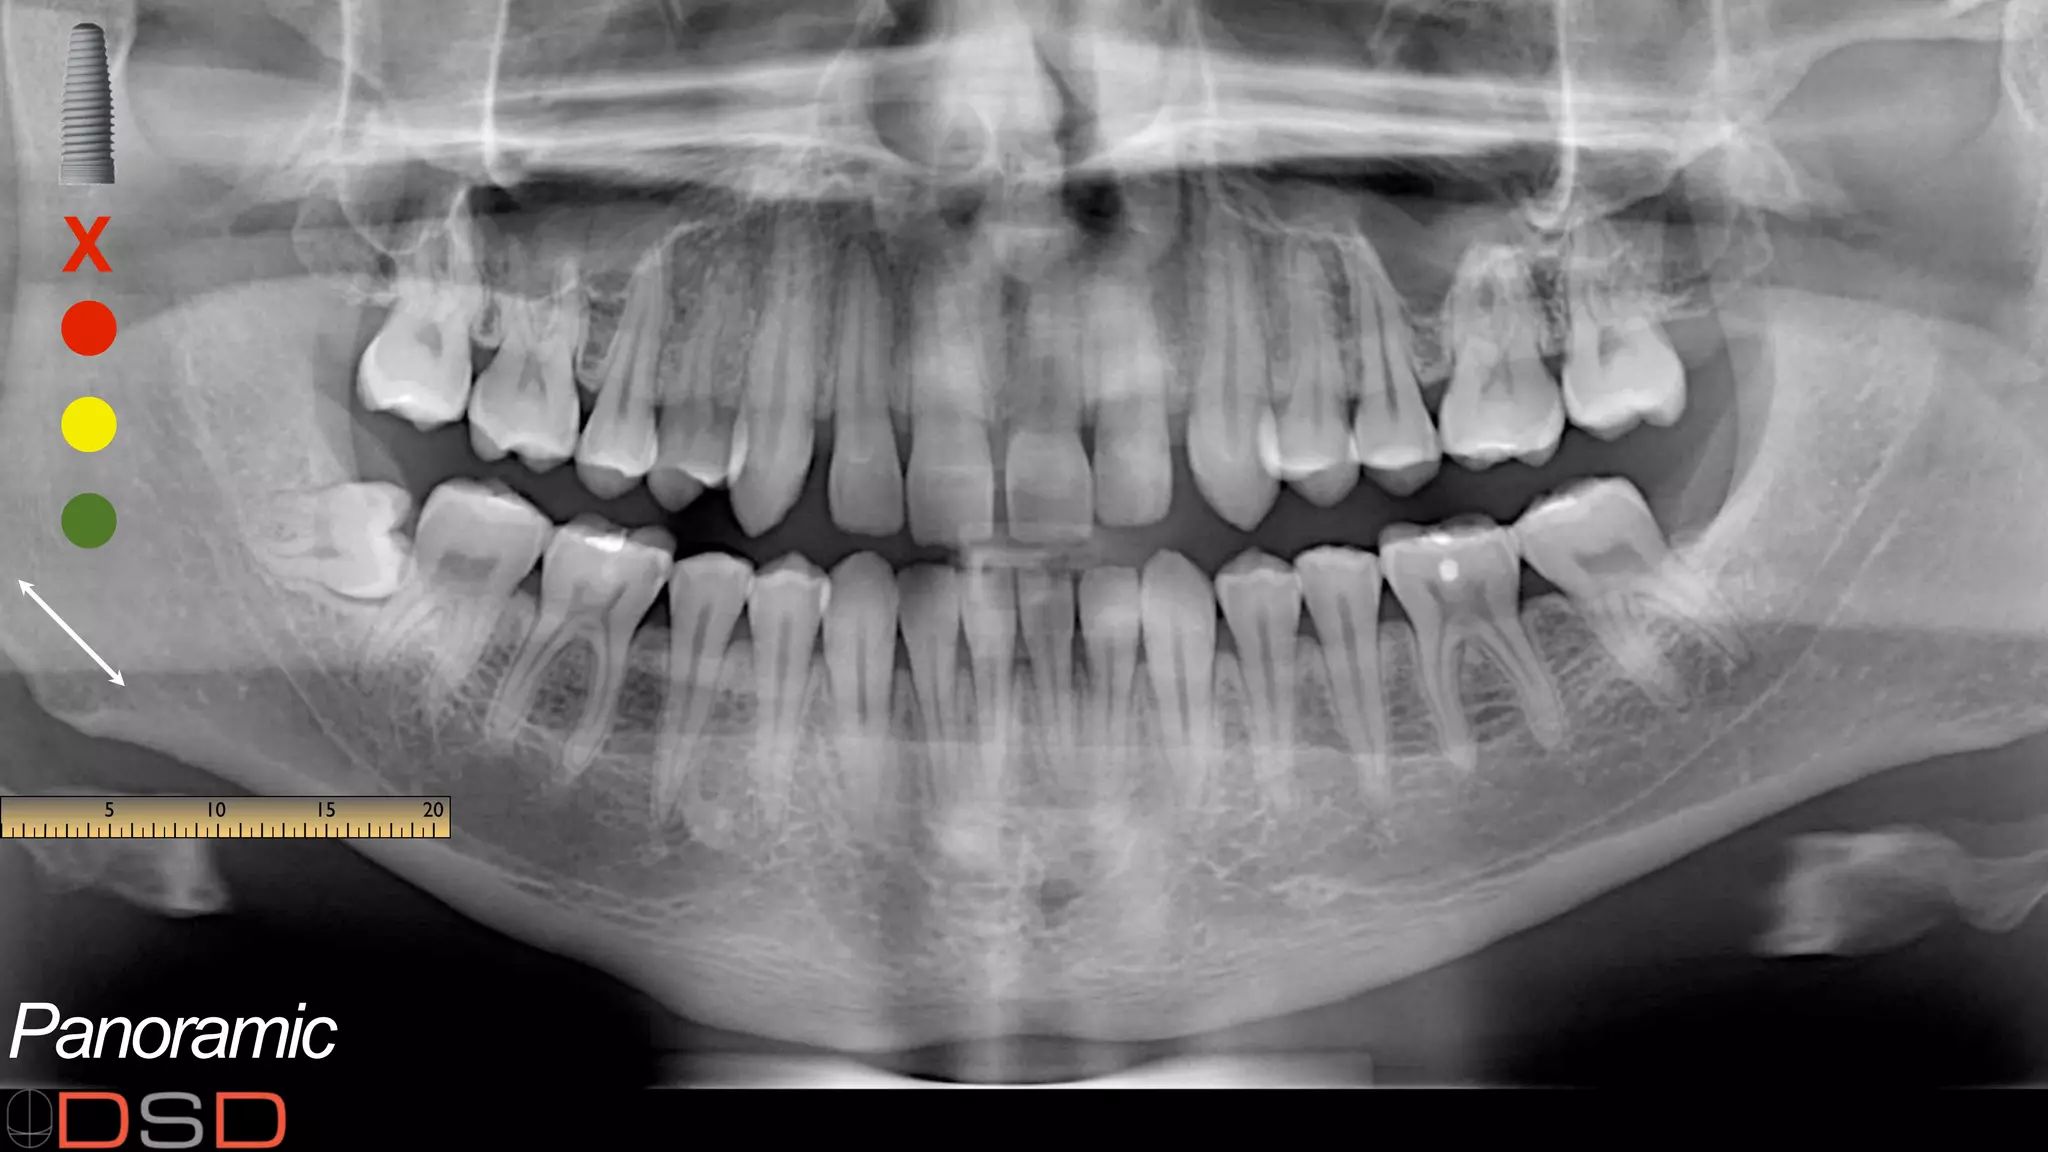

Additional visual aids including various photos, facial videos, close-up videos, functional videos, X-rays, perio charts, and panoramic images.